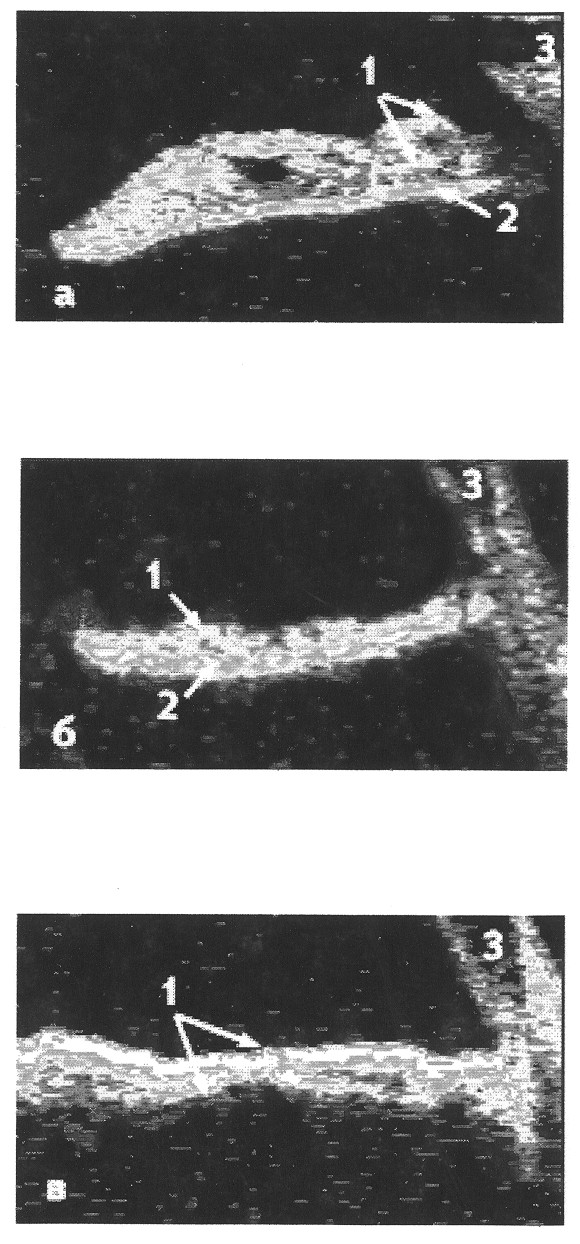

Способ поясняется ОСТ радужки, где а - норма: 1 - строма, 2 - пигментный слой, 3 - роговица; б - ОСТ радужки больного глаукомой Франк-Каменецкого; в - ОСТ радужки больного эссенциальной мезодермальной дистрофией с измененной стромой радужки 1. (см.чертеж).

Всем пациентам проводят стандартное офтальмологическое обследование, а также гониоскопию, томографию, ультразвуковую биомикроскопию. У всех пациентов выявляют изменения радужки. При глаукоме Франк-Каменецкого отмечают двухцветное окрашивание радужки. Зрачковая зона узкая, всегда светло-серая или желтая, тусклая, лишена нормального блеска. Периферия в виде широкого контрастного кольца шоколадно-коричневого или сине-лилового цвета из-за гипоплазии соединительнотканной стромы радужки. Строма радужки слабо развита и сохранена лишь в зрачковой зоне, по периферии почти отсутствует, обнажая задний пигментный листок. В дальнейшем пигментный листок постепенно исчезает вплоть до полной аниридии. У всех пациентов с глаукомой Франк-Каменецкого отмечают явления гониодисгенеза, глаукома протекает по типу открытоугольной. При первичном осмотре у пациентов с ээсенциальной мезодермальной дистрофией радужки отмечают отек переднего эпителия и стромы роговицы. Визуально изменения радужки во всех случаях выявляют на одном глазу. Гониоскопически у всех пациентов определяют высокою плоскостную гониосинехию. Определяют смещение зрачка в сторону гониосинехии, выворот пигментной каймы и зоны истончения радужки, сквозные дефекты радужки неправильной формы различных размеров вплоть до остатков тканей в виде тонких нитей. Глаукома протекает по типу закрытоугольной. Для уточнения диагноза и исследования механизма разрушения радужки всем больным проводят оптическую когерентную томографию радужки. В норме толщину стромы радужки регистрируют в пределах от 460 до 283μ, толщина пигментного эпителия варьирует от 65 до 75μ. При исследовании пациентов с глаукомой Франк-Каменецкого определяют, что строма радужки резко истончена вплоть до полного исчезновения (от 230 до 0μ). Пигментный листок, наоборот, резко утолщен от 108-189μ у лимба до 200-340μ в зрачковой зоне, что в 1,5-4,5 раза превышает нормальные показатели. Наименьшую толщину пигментного листка регистрируют по краю сквозных дефектов, а наибольшую в центре сохранившихся участков. Данные ОСТ показывают, что при глаукоме Франк-Каменецкого имеет место врожденное недоразвитие стромы и аномальная гипертрофия пигментного листка, что ведет к снижению прочности, эластичности радужки и, следовательно, к ее разрывам в течение жизни на фоне обычных физиологических движений радужки. У пациентов с эссенциальной мезодермальной дистрофией радужки, по данным исследования на ОСТ, толщина пигментного листка в пределах нормы (60-79μ) и его состояние не меняется в процессе развития заболевания, даже на участках с грубыми, сквозными дефектами радужки. Основные изменения происходят в строме: на первых этапах на ОСТ отмечают увеличение ее плотности, что отображается на томограммах в виде снижения прозрачности и смещения цветовой палитры в сторону белого. На поверхности резко истонченной мезодермальной ткани определяют очень плотную, практически непрозрачную структуру, по своей плотности напоминающую рубцовую соединительную ткань, толщина стромы уменьшается до 350-130μ. Уплотнение мезодермального листка и уменьшение его толщины происходит на обоих глазах с разной степенью выраженности.

Status localis: OD - роговая прозрачная, радужка-структура и рисунок не нарушены, передняя камера средней глубины, зрачок круглый, диаметр 3 мм, фотореакция живая. Хрусталик прозрачный. Глазное дно - DSH бледно-розовый, перипапиллярная атрофия сосудистой до 1,0-1,5 ДД. OS - роговая прозрачная, более яркий и четкий контур заднего эпителия роговой в виде “чеканного серебра”, передняя камера средней глубины. Выраженная атрофия радужки: зрачок смещен книзу, выворот пигментной каймы, реакция зрачка сохранена, большое количество огромных, неправильной формы дефектов радужки в верхней половине (поликория), местами видны неизмененные цинновы связки, хрусталик прозрачный. Глазное дно: DSH - косой врез диска, краевой неглубокая экскавация, миопический конус 1/3 ДД. Гониоскопия: OD - угол острый, пигментация 1 степени. OS - в нижнем отделе угол деформирован и закрыт высокой гониосинехией, в верхнем отделе угол открыт, пигментация незначительная. На УБМ OD - радужка не истончена, угол ПК открыт, пролапса нет. УБМ OS - соответствует гониоскопической картине: в верхних отделах УПК открыт, в нижних отделах высокая гониосинехия, радужка истончена. На ОСТ радужки OS - строма радужки резко уплотнена, толщина снижена от 200μ (в зоне наиболее сохранившейся радужки) до 130μ в участках наиболее тонкой радужки, на передней поверхности стромы определяется очень плотная, непрозрачная структура, напоминающая по плотности рубцовую соединительную ткань. Пигментный листок 68-72μ на всех участках сохранившейся радужки, даже по краю разрывов. OD - строма от 340μ до 294μ (норма), но отмечается ее уплотнение и снижение прозрачности, смещение палитры цвета в сторону белого, пигментный листок 72-75μ (норма). Диагноз: эссенциальная мезодермальная дистрофия радужки OS, вторичная глаукома, миопия II степени, миопия III степени OD.

Таким образом, в представленных случаях у пациентов имелась сходная клиническая картина: молодой возраст, ВГД, зрительные функции, внешнее поражение радужки. Наибольшая и существенная разница выявлена по данным ОСТ радужки, что позволило достоверно различить эти две формы вторичной глаукомы, поставить точный диагноз и выявить различный механизм повреждения радужки.